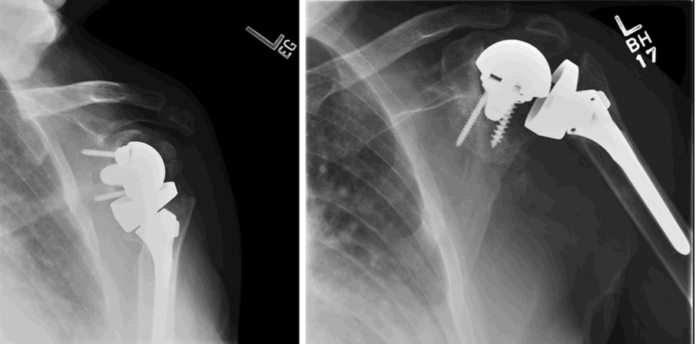

(2) The most common complications of rTSA, acromial and scapular spine fractures, are unique and difficult to solve problems for patients having reverse arthroplasty. In contrast, the most common complications from aTSA – glenoid component loosening and rotator cuff tear – can be effectively managed by revision to a rTSA